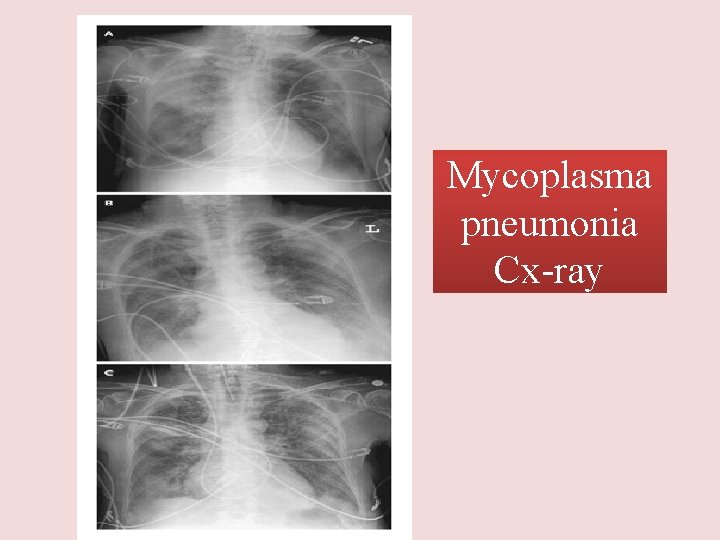

Mycoplasma pneumonia • • • Eaton agent (1944) No cell wall Common Rare in children and in > 65 People younger than 40. Crowded places like schools, homeless shelters, prisons. • Mortality rate 1. 4% • Usually mild and responds well to antibiotics. • Can be very serious • May be associated with a skin rash, hemolysis, myocarditis or pancreatitis

Mycoplasma pneumonia Cx-ray